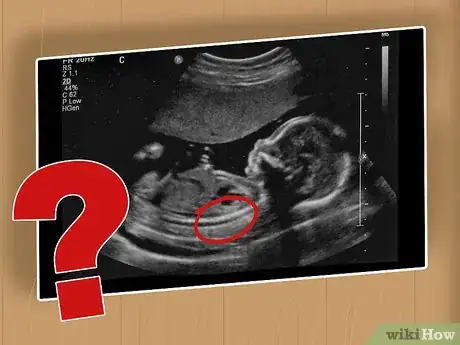

2Have an ultrasound. If your AFP levels are high, then your doctor will probably want to do an ultrasound. An ultrasound can provide images of an unborn baby’s spine and spinal cord, which may enable the doctor to diagnose spina bifida.[8]